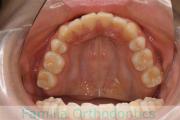

歯並びを治したいということで来院されました。下あごがやや右側に偏位して後退している、上顎前突(出っ歯)でした。上下左右から小臼歯を抜歯して、歯科矯正用アンカースクリューを併用したマルチブラケット法にて治療を行いました。約2年、24回の来院をしていただきました。

下顎の後退はいびきなどの上部気道の障害が出やすいと考えられます。